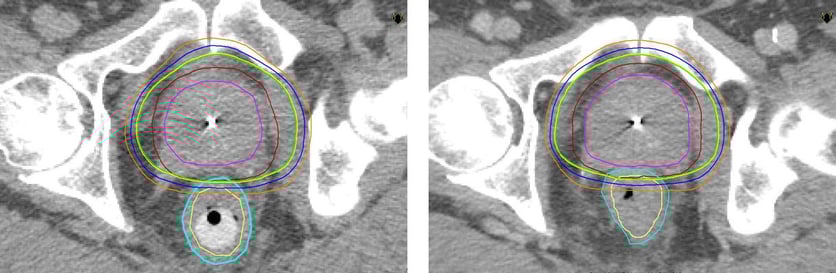

2005 var Akademiska pionjär i Sverige med strålbehandling med rektalstav mot prostatacancer. Sjukhuset är fortfarande ensamt om att erbjuda denna form av strålbehandling som ger färre biverkningar än andra jämförbara metoder. Metoden gör det möjligt att ge högre dos i prostata och skona frisk vävnad/intilliggande organ.

– Precis som vid annan strålterapi är målet med stavbehandling att döda cancercellerna. Vi behandlar 25-30 patienter per år med denna metod. Fördelen är att man kan öka avståndet mellan prostata och ändtarmen och därigenom ge högre stråldos i prostata och lägre i ändtarmen så att frisk vävnad skonas. Jämfört med konventionell strålbehandling utan rektalstav, som är vanligast idag, kan man ge lite högre stråldos utan fler biverkningar, säger Kristina Nilsson, överläkare i onkologi vid Akademiska sjukhuset.

Inom strålbehandlingen på Akademiska bedömer experterna att de goda resultaten med stavbehandling delvis beror på att rektalstaven bidrar till att fixera prostata under behandlingen.

* Rektalstaven förs in i ändtarmen som trycks nedåt och separeras från prostatan. På så sätt kan stråldosen minskas till ändtarmen.